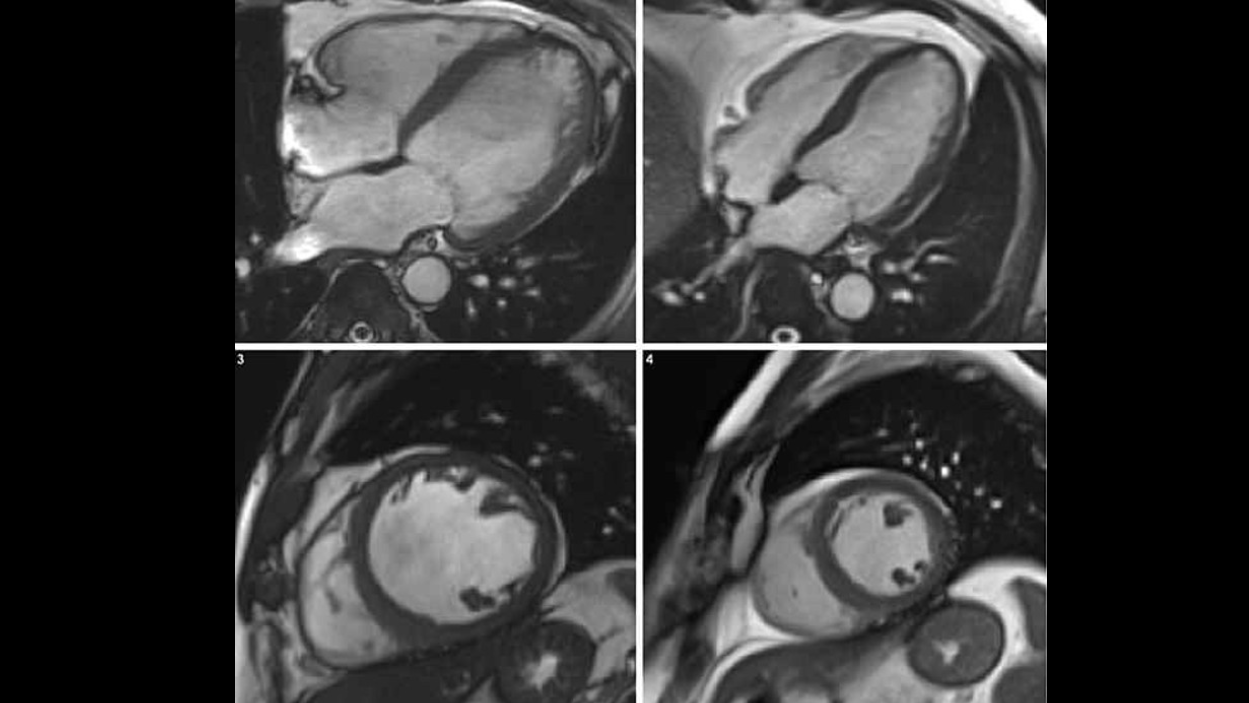

Zu viel Alkohol schadet dem Körper. Eine neue Studie hat nun aufgezeigt, was Alkoholismus mit dem menschlichen Herzen machen kann.